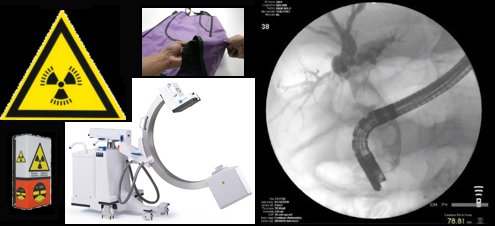

RADIOPROTEZIONE DEL LAVORATORE

A RISCHIO DI ESPOSIZIONE ALLE RADIAZIONI IONIZZANTI: FORMAZIONE SPECIFICA IN RADIOLOGIA

D.Lgs. 101/2020 smi – ART. 111

RADIOPROTEZIONE DEL LAVORATORE A RISCHIO DI ESPOSIZIONE ALLE RADIAZIONI IONIZZANTI: FORMAZIONE SPECIFICA

PER LE PRATICHE DI GASTROENTEROLOGIA – ENDOSCOPIA DIGESTIVA

D.Lgs. 101/2020 – ART. 111

Secondo l’art.111 del D.Lgs. 101/2020 e smi il datore di lavoro provvede affinché ciascun lavoratore soggetto ai rischi derivanti dall’esposizione alle radiazioni ionizzanti riceva una adeguata informazione sui rischi per la salute e la sicurezza sul lavoro connessi all’attività svolta, sui rischi specifici cui è esposto in relazione all’attività svolta, sulle norme interne di protezione e sicurezza, sulle disposizioni aziendali in materia e sulle conseguenze legate al loro mancato rispetto, sulle misure e sulle attività di protezione e prevenzione adottate. Secondo lo stesso articolo il datore di lavoro assicura che ciascun lavoratore soggetto ai rischi derivanti dall’esposizione alle radiazioni ionizzanti in relazione alle mansioni cui è addetto riceva una formazione sufficiente e adeguata in materia di radioprotezione. L’informazione e la formazione previste sono svolte nell’ambito delle rispettive competenze dagli esperti di radioprotezione e dai medici autorizzati riconosciuti come formatori in materia di salute e sicurezza.